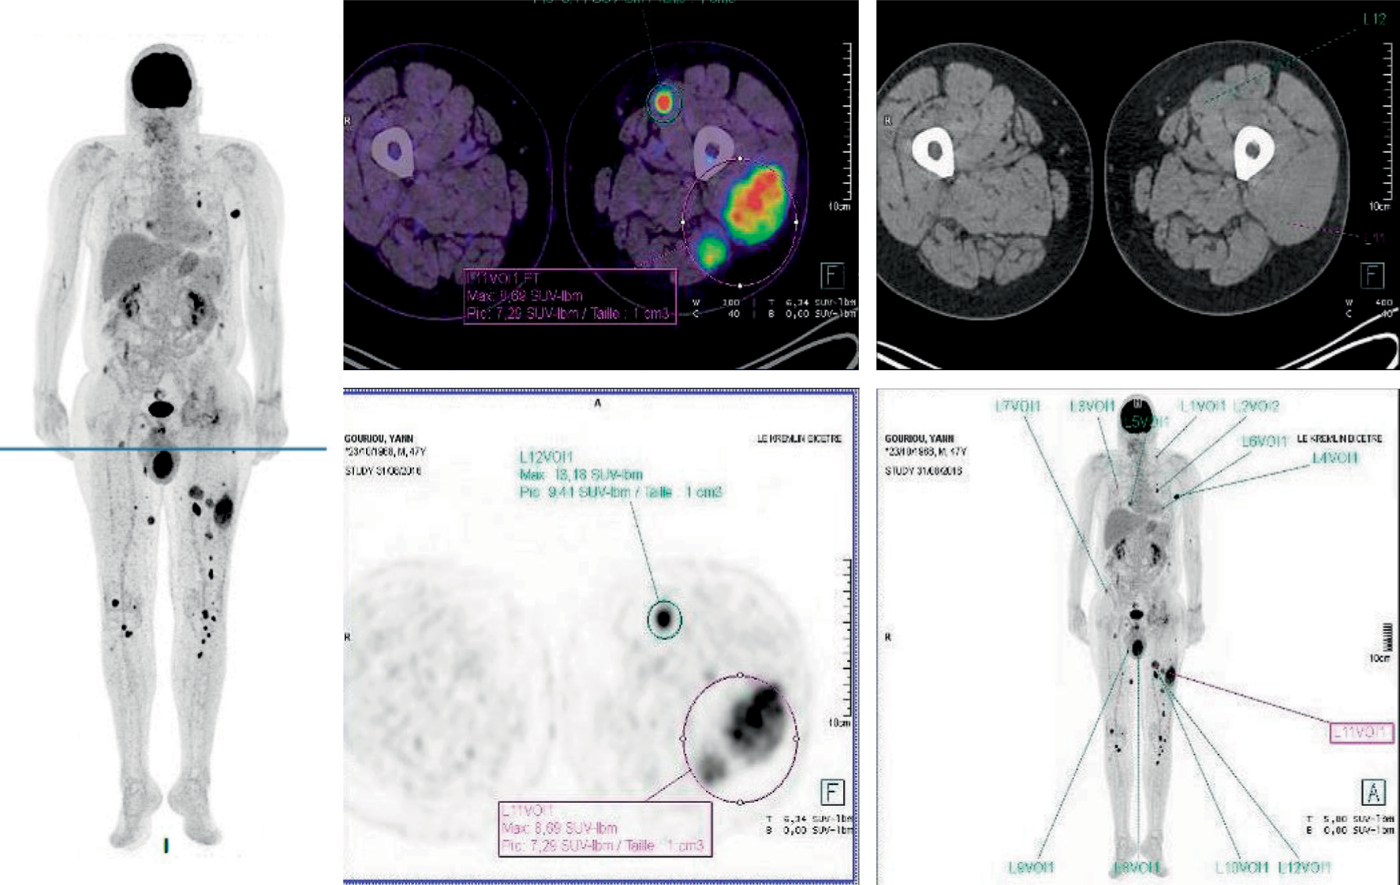

Le TEP-scan est plus sensible que les radiographies standards :

Fig. 28.5.

Image « corps entier » d’un TEP-scan. Patient atteint de myélome multiple en rechute sous forme extramédullaire